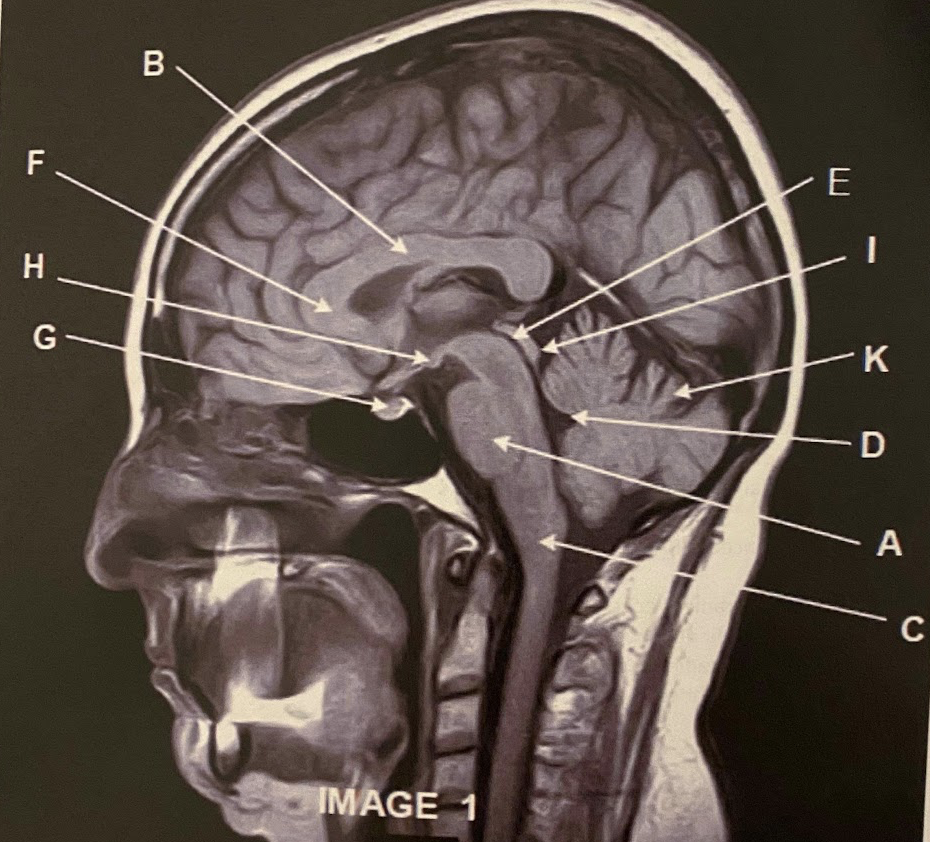

Q

The sagittal scan, demonstrates typical hyper intense tendril-like projections in the corpus callous characteristically seen in patients with what disease?

A) Tuberous Sclerosis

B) Multiple Calcified Nodules

C) Multiple Sclerosis

A

What anatomy is letter A pointing to?

Pons

Corpus Callosum

4

What anatomy is letter C pointing to?

Medulla Oblongata

What anatomy is letter E pointing to?

Aqueduct of Sylvius

Genu of the corpus callous

What anatomy is letter G pointing to?

Pituitary

Mammillary Bodies

Quadrigeminal plate

This image is non-contrasted. It was acquired using a _______ sequence

A) Proton Density

B) T1

C) FLAIR

D) GRE